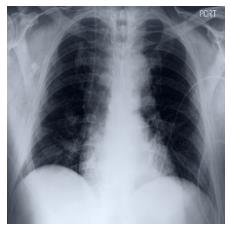

Performance degradation due to distribution discrepancy is a longstanding challenge in intelligent imaging, particularly for chest X-rays (CXRs). Recent studies have demonstrated that CNNs are biased toward styles (e.g., uninformative textures) rather than content (e.g., shape), in stark contrast to the human vision system. Radiologists tend to learn visual cues from CXRs and thus perform well across multiple domains. Motivated by this, we employ the novel on-the-fly style randomization modules at both image (SRM-IL) and feature (SRM-FL) levels to create rich style perturbed features while keeping the content intact for robust cross-domain performance. Previous methods simulate unseen domains by constructing new styles via interpolation or swapping styles from existing data, limiting them to available source domains during training. However, SRM-IL samples the style statistics from the possible value range of a CXR image instead of the training data to achieve more diversified augmentations. Moreover, we utilize pixel-wise learnable parameters in the SRM-FL compared to pre-defined channel-wise mean and standard deviations as style embeddings for capturing more representative style features. Additionally, we leverage consistency regularizations on global semantic features and predictive distributions from with and without style-perturbed versions of the same CXR to tweak the model's sensitivity toward content markers for accurate predictions. Our proposed method, trained on CheXpert and MIMIC-CXR datasets, achieves 77.32$\pm$0.35, 88.38$\pm$0.19, 82.63$\pm$0.13 AUCs(%) on the unseen domain test datasets, i.e., BRAX, VinDr-CXR, and NIH chest X-ray14, respectively, compared to 75.56$\pm$0.80, 87.57$\pm$0.46, 82.07$\pm$0.19 from state-of-the-art models on five-fold cross-validation with statistically significant results in thoracic disease classification.